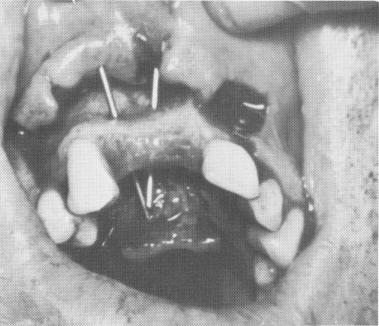

Fig. 12-88. Both pins remained transfixed through the bone prior to the elastic impression.

Fig. 12-89. The pins were first removed from the mouth after the elastic impression hardened and were then slipped back into the impression after it was removed.

2 Pins removed from impression in mouth & later kept back outside mouth